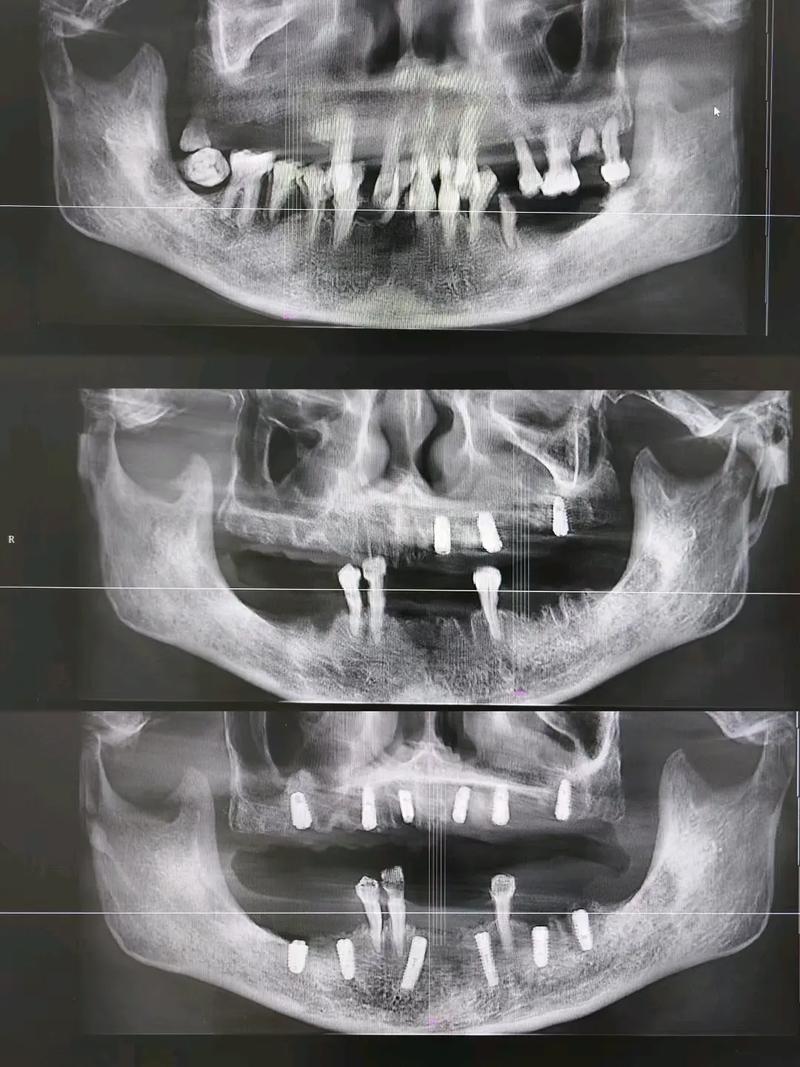

种植体与颌骨形成骨结合是种植成功的关键,这一阶段(通常为3个月,上颌骨可能需4-6个月)的随访检查尤为重要,临床医生常通过临床检查(如叩诊、松动度评估)结合影像学检查判断骨结合情况,此时若患者无明显症状,常规口腔曲面断层片(OPT)可能已足够,但对于骨结合情况复杂、存在骨缺损或需要精确评估骨整合程度的病例,CBCT是更优选择,CBCT能三维显示种植体周围骨小梁的结构、密度以及种植体与骨界面的接触情况,判断骨结合是否良好,为负重时机提供依据,对于骨质疏松患者或骨量不足需植骨的病例,CBCT可清晰显示植骨材料的吸收与新生骨的形成情况。

种植体完成负重进入长期使用阶段后,定期随访是保障其寿命的重要措施,此时若患者出现种植体周围软红肿、出血、溢脓,或咬合不适、种植体松动等症状,需及时进行CT检查,排查种植体周围炎、骨吸收等并发症,种植体周围炎是导致种植失败的主要原因之一,早期仅表现为牙龈炎症,若不及时干预,可能进展为牙槽骨吸收,导致种植体松动脱落,CBCT可精确测量骨吸收的程度、范围( whether 为垂直吸收或环形吸收),以及骨缺损的类型(如一壁骨缺损、二壁骨缺损等),为制定治疗方案(如牙周刮治、骨增量、甚至种植体取出)提供精准指导,对于种植体修复后咬合异常、修复体折断或需进行二次修复(如更换基台、冠)的情况,CT可评估种植体角度、位置是否符合修复要求,避免因修复体设计不当导致种植体受力异常。

- 种植体周围炎诊断:临床表现为牙龈出血、牙周袋溢脓、种植体动度增加时,CBCT可明确骨吸收程度和范围,指导牙周治疗或手术方案制定。